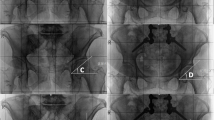

All parameters of interest were measured on preoperative (within 2 months before LSF) and postoperative (1 year following LSF) standing lateral radiographs (EOS®) by two orthopedic residents (D.D, S.H). Lumbar lordosis (LL), was defined as the angle formed by the line tangent to the superior endplate of L1 and the line tangent to the superior endplate of S1 for each film (Fig. 1). The anterior pelvic plane (aPP) was defined as the angle between the plane created by the bilateral anterior superior iliac spine to the pubic symphysis and the coronal vertical plane (Fig. 1) [3]. The pelvic tilt (PT) was defined as the angle formed by the sacral endplate midpoint to the center of the bifemoral heads and the vertical axis (Fig. 1), whereas the sacral slope (SS) as the angle formed by the line tangent to the superior endplate of S1 and the horizontal (Fig. 1). The pelvic incidence (PI) was defined as the angle between the line perpendicular to the sacral plate at its midpoint and the line connecting this point to the femoral head axis [11]. Finally, the acetabular anteinclination (AI) was determined by the line connecting the superior and inferior acetabular wall on the right side to the horizontal axis (Fig. 1) [2].

An example of pre-and postoperative standing lateral radiographs (EOS®) of a patient who underwent a LSF at the level L5/S1. For illustration purposes, the thoracic spine is not demonstrated. The acetabular anteinclination (blue lines) was measured on the pre-and postoperative radiographs. The sacral slope (green lines) and anterior pelvic plane (orange lines) are demonstrated in the preoperative radiograph, whereas the lumbar lordosis (purple lines) and pelvic tilt (red lines) are shown on the postoperative radiograph for the simplicity of the figures